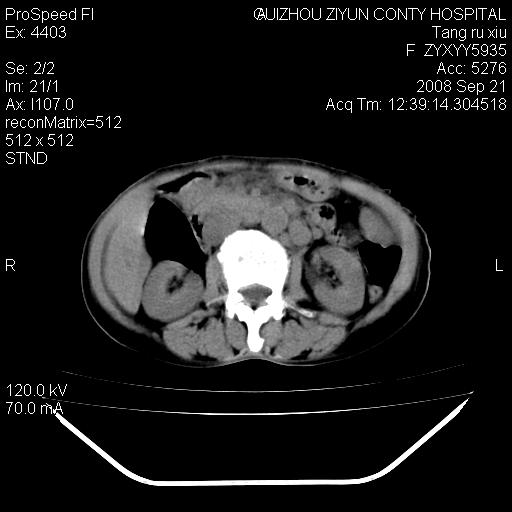

f、57岁,上腹痛.2月,近来胸闷。2月前在外院摄胸片示左侧胸腔少量积液。

肝脏大小形态尚可,其实质内可见多发大小不等的低密度影,边缘模糊。肝门区结构紊乱,腔静脉腹主动脉旁可见多发软组织密度影,部分融合成团块状,并向下延伸。胰腺及十二指肠结构显示不清。腹腔内脐后肠管走形僵硬,管壁可见增厚。盆腔内可见多个淋巴结影。所扫层面左侧胸腔可见大量弧形水样密度影,其内侧可见被压缩的肺组织影。左侧胸壁可见一小结节样软组织密度影,边缘模糊。心脏纵隔向右侧移位。心脏包膜内可见囊样低密度影,其内侧心房室周围可见一圈气体样密度影。纵隔内大血管旁可见多发软组织团块影,部分融合。

1.腹膜后淋巴瘤侵及肝脏,肺内及纵隔内多发转移。2.左侧大量胸腔积液并压缩性肺不张。3.心包脓肿可能,转移不除外。4.脐后局部肠管管壁增厚,考虑炎症可能,肿瘤不除外。

为什么没有人注意到腹腔脐后的那段肠管呢?那段看着很不好的样子。